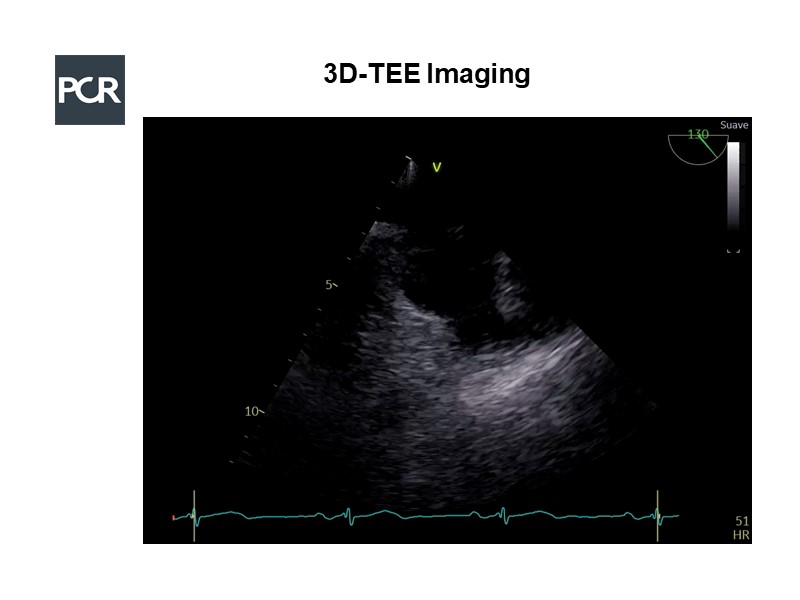

Imaging in LAA occlusion: from planning to final assessment

Consult this session to learn about imaging supporting LAA occlusion procedure, how to combine different imaging techniques to guide this intervention and their value for procedure planning.